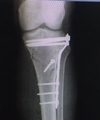

- Reducción ortopédica e inmovilización de fracturas y/o luxaciones

- Reducción ortopédica osteosíntesis percutanea e inmovilización de fracturas y/o luxaciones